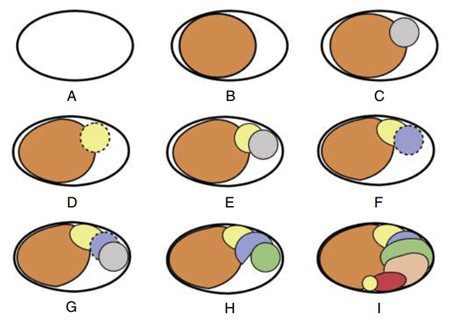

Trong kỹ thuật lèn ngang nguội cổ điển, côn chính là côn 0.02 với kích thước đầu tương ứng với kích thước trâm chóp chính (MAF) mà ống tủy đã được sửa soạn. Côn được chọn nên đặt vừa đến chiều dài làm việc, không thể đẩy quá chiều dài làm việc và có cảm giác kháng lực nhẹ khi rút ra khỏi ống tủy. Lực kháng này (gọi là tug-back) cho thấy côn đang kẹt vào thành ống tủy (hình 14.11).

- Thêm côn phụ: Các côn phụ được thêm vào không gian do cây lèn tạo ra (hình 14.17).

Có thể sử dụng các loại côn phụ khác nhau, phù hợp với kích thước cây lèn. Thông thường, côn không chuẩn hoặc côn chuẩn số 25, độ thuôn 0.02 được sử dụng làm côn phụ.

Trong các ống tủy rất lớn, có thể sử dụng côn phụ lớn hơn và cây lèn cỡ lớn hơn. Cần thận trọng trong quá trình lèn ngang, tránh tạo lực quá mạnh trong ống tủy (khuyến cáo này cũng áp dụng cho các kỹ thuật khác). Lực sử dụng được khuyến nghị không quá 2,5 pound để làm tránh gãy chân răng theo chiều dọc (hình 14.18).

Khi thêm nhiều côn phụ, cây lèn sẽ đặt vào ống tủy càng ít sâu hơn. Quá trình lèn nên tiếp tục cho đến khi cây lèn không thể đặt sâu hơn khoảng 4 mm dưới mức miệng ống tủy (hình 14.20).